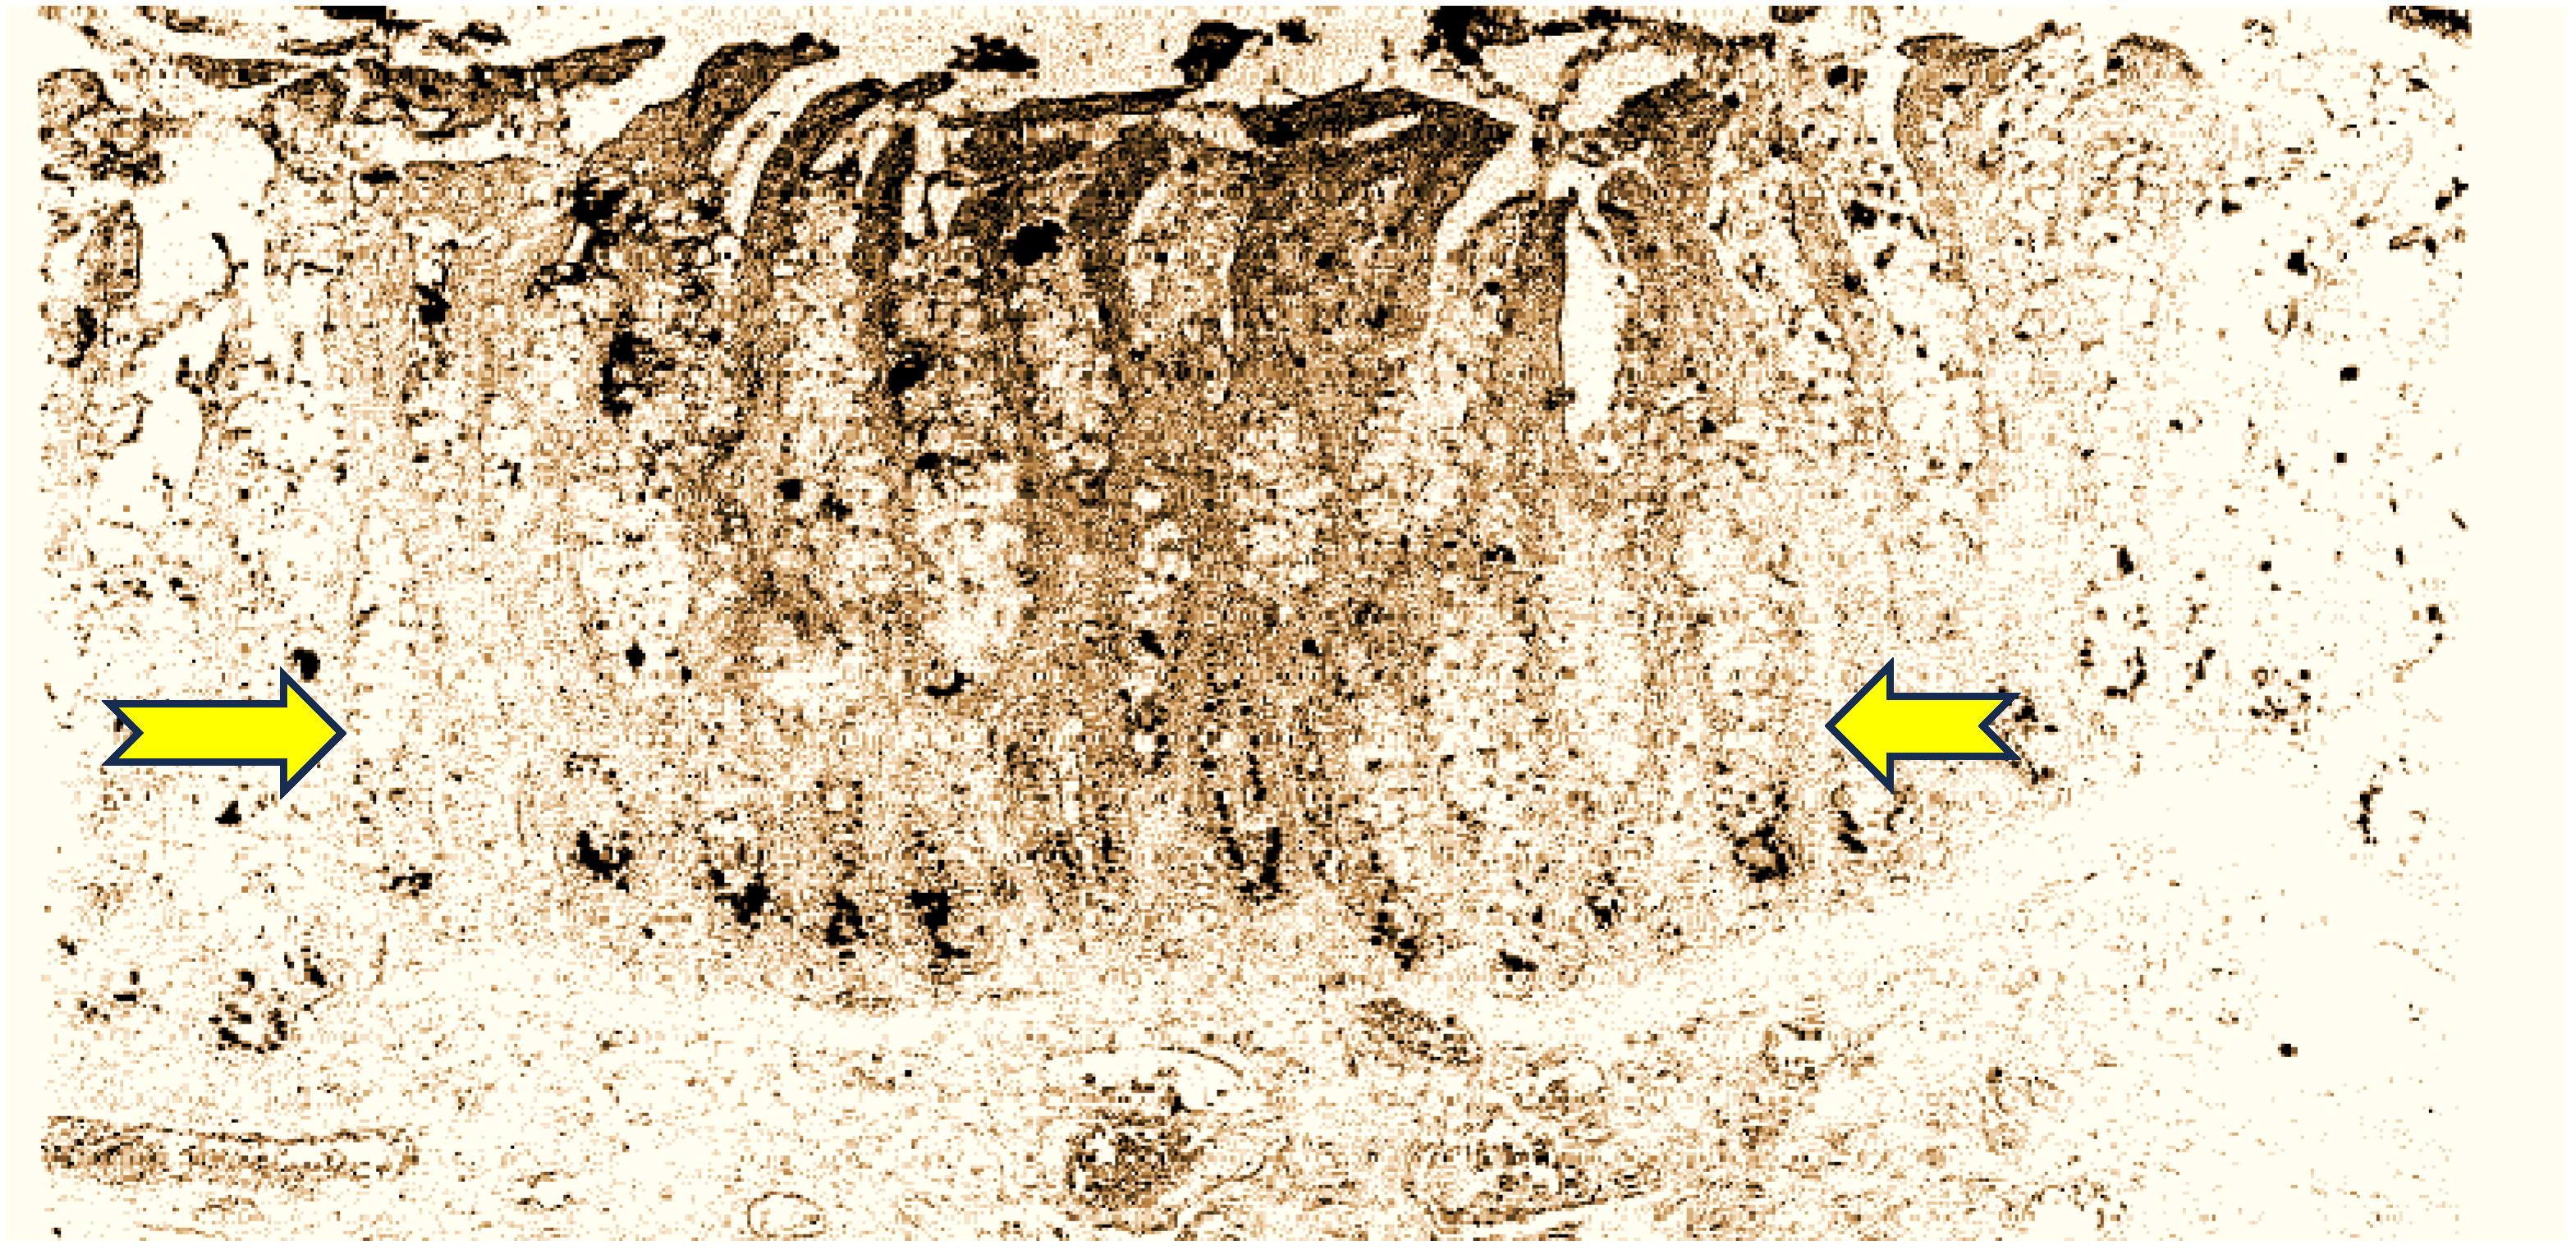

The anti-CEA used in this series was the highly sensitive and specific MAb T84.66. It has been consistently used for human CEA testing, mainly in human sera, and is the basis for the Roche CEA immunoassay, and superior when compared to the CEA RIAKIT. However, the authors did disclose that they “slightly modified” the Roche kit, and found the first to have a greater affinity for tissue CEA than blood CEA [18]. This observation was tested 15 years later in a Callitrichid application, leading us to reopen the discussion on the CTT as a relevant model [19]. It should not come as a surprise that anti-CEA antibodies have a vast spectrum of specificity, with some “questionable” antibodies being some of the first to recognize the Callitrichid CEA moiety. SPAN-1 is a sialylated high-molecular-weight mucin and is related to the epitope related to CA19-9 of the IgG1 isotype. This antibody and other related epitopes were also used in IHC in the CTT, such as MAb 29-1, an IgM isotope which reacts with a lacto-N; fucopentaose III, an Lex antigen; and E5-6, detecting an Leb antigen. Only the latter showed staining in 50% of tumor cells [20]. Other antibodies were also used, but the results were not fully conclusive. CaCo 3/61 readily stains CTT colon tissues and rat jejunal cells, and in humans, seems specific for adenocarcinoma, but seems to bind CTT tissues universally. The strongest 4+ staining occurred in the lumen of the crypts, suggesting a semi-permanent location (see Figure 1).

Figure 1. CaCo 3/61 staining of CTT colonic crypts shows that the bottoms of the crypts are intensely stained (between yellow arrows), similarly to rat crypts, as has been previously described. The cellular distribution is focally cytoplasmic and the intensity is 3–4+, as described in the methods section.

Chromogranin-A did not differentiate between cancer CTT tissue or normal resident neuroendocrine cells. However, Adnab-9 MAb binding (adenoma biomarker 9) and now the likely innate immune system indicator, was higher in normal humans (p < 0.05) than IBD washings, and also positive in IBD human extracts. K-Ras p21 was elevated in humans with IBD (p < 0.05). EGFR was maximal in CTT extracts (p < 0.005), known to occur in 80–90% of human CRC [27]. Aminoproteoglycans (APGs) were also maximal in the CTT extracts, and given their widespread distribution in CTT (see Figure 1), this is not surprising. Telomerase is known to be low in human washings or tissue [33], and 86% of our human IBD samples were negative, but in contrast, over half of the CTT washings were positive, supporting their role in the early detection of cancer [24].